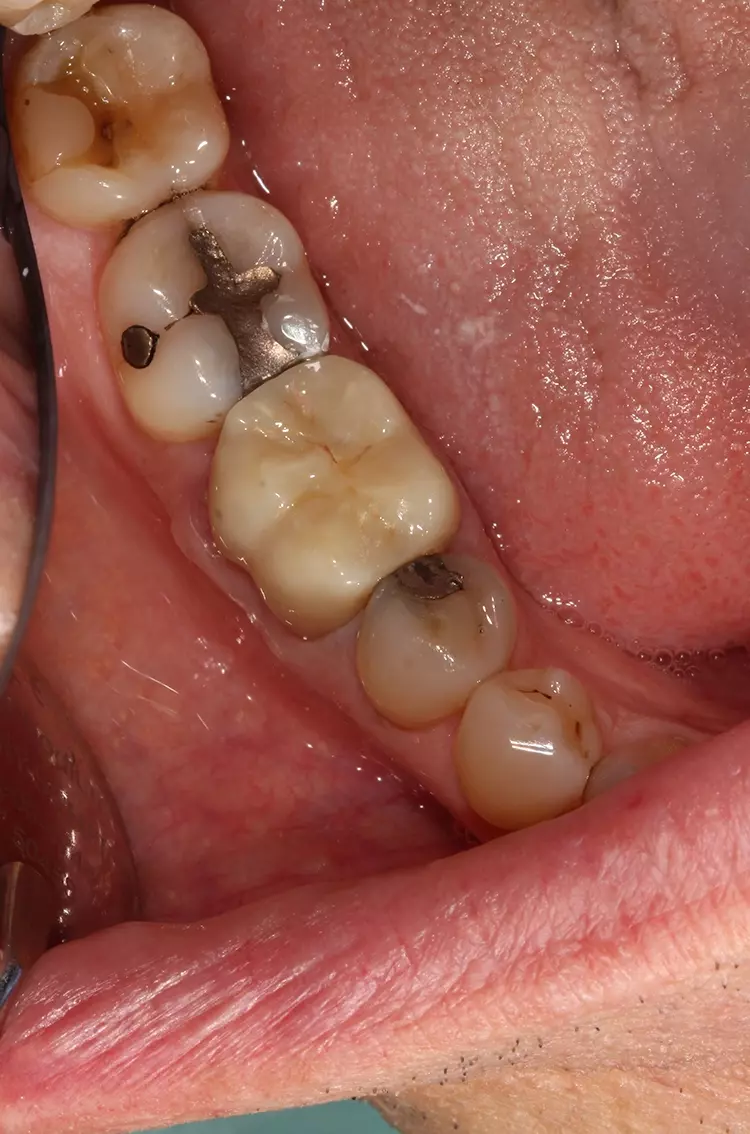

Die klinische Situation mit einem erkennbar erweiterten, trockenen gingivalen Sulkus war ideal für den nachfolgenden intraoralen 3D-Scan (Abb. 7 und 8). Die CAD-Screenshots der mit dem Trios-Intraoralscanner (3Shape) erstellten 3D-Scans bestätigten den klinischen Eindruck (Abb. 9a und 9b).

Wie gewünscht und notwendig, wurde ein klarer und gut definierter Rand erfasst [9]. Nach dem Design am Computer mit exocad (Align Technology) wurde die Krone gefräst und manuell durch Bemalen und Glasieren fertiggestellt [2].

Patient und Zahnarzt waren mit dem Endergebnis sehr zufrieden. Die klinischen Aspekte der Behandlung verliefen stressfrei. Die VOCO Retraction-Paste ist das ideale Produkt zur temporären Retraktion der marginalen Gingiva und schafft einen trockenen Sulkus für präzise Abformungen.